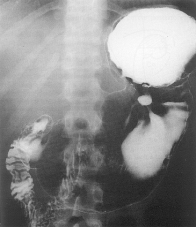

Hernia hiatala reprezinta patrunderea stomacului în cavitatea toracica prin hiatusul diafragmatic.

Pe radiografiile simple toracice, în herniile fixate în torace, se evidentiaza o imagine aerica sau hidroaerica localizata în mediastinul inferior si posterior.

HERNIA PRIN ALUNECARE - este cel mai comun tip de hernie. Fornixul, împreuna cu cardia, sunt situate intratoracic. Esofagul este sinuos, cudat (kinking), orificiul cardial este situat posteromedian. Refluxul gastroesofagian este frecvent. El produce esofagita care poate evolua spre stenoza.